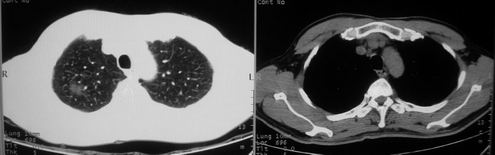

男,62岁,咳血两天。无其他不适。

右肺上叶浅淡密度增高影,考虑炎性病变

片状磨玻璃影,考虑肺泡出血可能性大,其他不排除,建议hrct

右上磨玻璃样密度影,考虑就是个肺泡出血,别的没有

病灶呈“磨玻璃影”,较薄,周围无卫星灶,很难一口说是肺结核,建议积极治疗后,短期复查!(支持考虑:肺泡出血!)

右肺上叶可见多发磨玻璃状影,符合肺泡内出血表现,严格意义上讲应该是肺泡内积血。引起出血的原因很多,不一定非得结核所致。